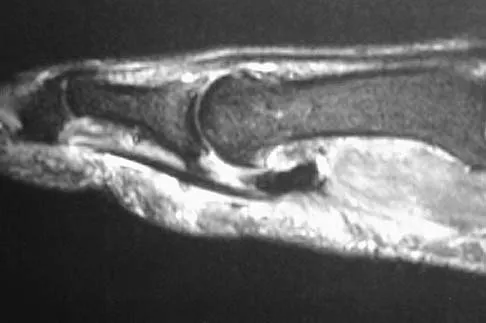

A patient notes pain under the first metatarsophalangeal joint following a soccer injury. The MRI scans shown in Figures 27a and 27b reveal what pathologic finding?

Explanation